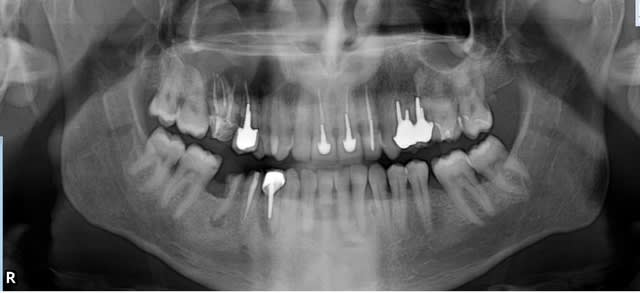

sur la première pano, on voit une grosse image radio claire de 17 à 14 a priori. ça serait intéressant de voir deux ou trois coupes du scanner ou le cone beam, mais je pense à un banal kyste d'origine dentaire très probablement en rapport avec la 16 d'autant que l'extension semble se faire en distal.

le kyste peut très bien refouler et respecter le plancher sinusien, dans ce cas les cones sont dans le kyste.

volumineux mais banal kyste dentigère qui a refoulé le plancher du sinus sans l'envahir (à confirmer peut être à l'anapath)! il va être content le Monsieur de savoir qu'il a pas un cancer ;-)

avec un peu de bol et en y allant délicatement, il n'y aura peut être même pas de cbs. par contre, ça va lui faire une joli trou trou ! je pense qu'au niveau de la 16 le peu de corticale vestibulaire qui reste va partir en sucette. ça va être chaud pour passer la curette au dessus de la 17 et de la 15 en passant par l’alvéole de la 16, même élargie en vestibulaire. enlever le kyste "à l'ancienn" en virant les denst et en explosant la table externe, c'est pas difficile, le faire en conservant un maximum de dents et en préservant au maximum le tissu osseux résiduel, c'est beaucoup plus chaud !

Personnellement je n'extrairais pas 16 ce qui permettra de ne pas avoir de communication Bucco sinusienne, de plus enlever ce kyste par voie alvéolaire semble plus qu'illusoire. Il semble plus raisonnable de passer par voie latérale pour éliminer ce kyste.Personnellement au vue de la taille du kyste, et surtout qu'il monte très haut, j'avoue que je passerais la main au stomato car il faut être capable d'ouvrir assez largement et assez haut pour éliminer la totalité du tissu kystique. Sans compter que l'artère alvéolo antrale se ballade quelque part, elle ne semble pas avoir été refoulée par le kyste.